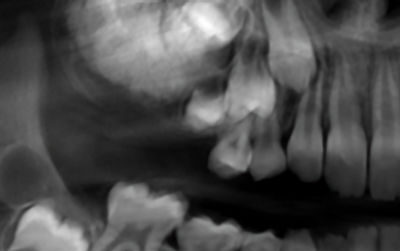

9-year-old girl with a posterior maxillary lesion

A 9-year-old girl presented to the oral surgeon, referred by her family dentist, because of a lesion in the right posterior maxilla.